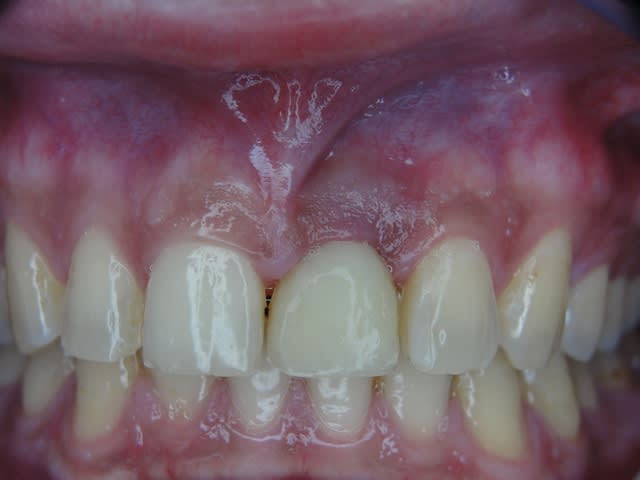

J'ai de tout en boutique..jeune homme 25 ans accident de piscine choc sur la bordure ( fêlure existante..fistule), extraction le jour même, temporisation 4 mois (avec un bout de trombone) Monobloc 16mm 60N, prep cap zircone droit 2/2 provisoire ion, temporisation 3 mois ceramo ceram..

J'ai de tout en boutique..jeune homme 25 ans accident de piscine choc sur la bordure ( fêlure existante..fistule), extraction le jour même, temporisation 4 mois (avec un bout de trombone) Monobloc 16mm 60N, prep cap zircone droit 2/2 provisoire ion, temporisation 3 mois ceramo ceram.. suite des photos :)